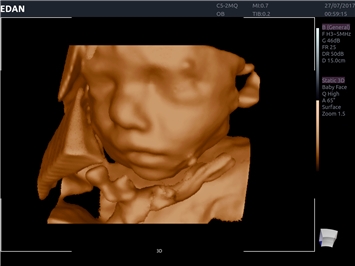

EDAN Acclarix LX4 представляет собой инновационную ультразвуковую систему, построенную на усовершенствованной платформе Acclarix. Сочетание высокого качества визуализации с интеллектуальным рабочим процессом делает эту систему оптимальным выбором для клиник, ценящих эффективность и экономичность.

• 3D/4D-визуализация с автоматическим редактированием объема (eFace)

• Автоматизированные измерения в акушерстве

• Акушерства и гинекологии

Общая визуализация, Гинекология и акушерство, УЗИ для кардиологии

3D/4D:

Да